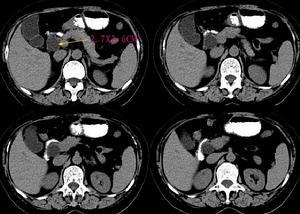

侵蝕性葡萄胎3.超聲檢查B型超聲為非侵入性檢查,可以早期發現葡萄胎組織侵入子宮肌層程度,協助診斷子宮內滋養細胞腫瘤病灶。宮壁顯示局灶性或瀰漫性強光點或光團與暗區相間的蜂窩樣病灶,應考慮為侵蝕性葡萄胎或絨癌。

4.組織學診斷單憑刮宮標本不能作為侵蝕性葡萄胎的診斷依據,但在侵入子宮肌層或子宮外轉移的切片中,見到絨毛結構或絨毛退變痕跡,即可診斷為侵蝕性葡萄胎。若原發灶與轉移灶診斷不一致,只要任一標本中有絨毛結構,即應診斷為侵蝕性葡萄胎。